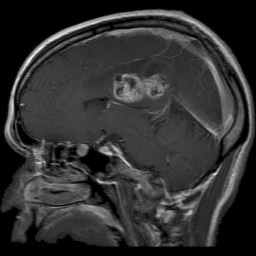

The dataset used in this project is the Brain Tumor Classification (MRI). It consists of MRI scans categorized into four classes: 👇

Glioma Tumor | Meningioma Tumor |

Normal | Pituitary Tumor |

![]() Actual: Glioma Tumor Predicted: Glioma Tumor (Confidence: 1.00) | ![]() Actual: Glioma Tumor Predicted: Glioma Tumor (Confidence: 1.00) |

![]() Actual: Meningioma Tumor Predicted: Meningioma Tumor (Confidence: 1.00) | ![]() Actual: Meningioma Tumor Predicted: Meningioma Tumor (Confidence: 0.81) |

![]() Actual: Normal Predicted: Normal (Confidence: 0.98) | ![]() Actual: Pituitary Tumor Predicted: Pituitary Tumor (Confidence: 0.99) |

![]() Actual: Pituitary Tumor Predicted: Pituitary Tumor (Confidence: 0.51) | ![]() Actual: Pituitary Tumor Predicted: Meningioma Tumor (Confidence: 0.43) |